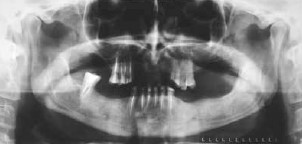

Paciente do sexo masculino de 64 anos, leucoderma, apresentando duas lesões radiolúcidas uniloculares, de bordas definidas, associadas aos dois terceiros molares mandibulares inclusos, as quais foram descobertas por meio de uma radiografia panorâmica de rotina. No exame intra-oral, o paciente não apresentava evidência de aumento de volume ou expansão das tábuas ósseas, vestibular e lingual. A radiografia panorâmica revela dois terceiros molares inferiores inclusos. Ambos se encontravam associados à lesão radiolúcida, unilocular, de bordas bem definidas. Sob anestesia local se realizou um retalho mucoperióstico vestibular ao nível do terceiro molar inferior direito, realizando a enucleacão da lesão juntamente com o dente retido. Posteriormente as bordas da ferida foram suturados com fio de seda 3-0, e as peças enviadas para estudo histopatológico. A lesão do terceiro molar inferior esquerdo foi tratada no mesmo dia sob anestesia local, realizando-se inicialmente uma punção com agulha nº 18 e seringa de 10 cc, para conhecer o conteúdo da lesão. Foi aspirado um líquido seroso amarelado contendo cristais de cálcio em seu interior. Posteriormente, uma incisão elíptica foi realizada ao nível do rebordo alveolar na região do terceiro molar e coletada parte da mucosa que recobria a lesão e encaminhada para estudo histopatológico. Finalmente, foi instalado um tubo de borracha confeccionado a partir de uma goteira, e em seguida foi fixado com fio de nylon 3-0 com ponto simples. A finalidade do tubo de borracha foi estabelecer a comunicação permanente da lesão com a cavidade bucal, com a finalidade de diminuir a pressão existente, favorecendo a neoformação óssea. O terceiro molar inferior esquerdo foi removido no mesmo ato cirúrgico. O tubo de borracha foi removido 3 semanas depois da cirurgia.

Ambos os casos os resultados histológicos confirmaram o diagnóstico clínico inicial.

Radiografia 4 meses após